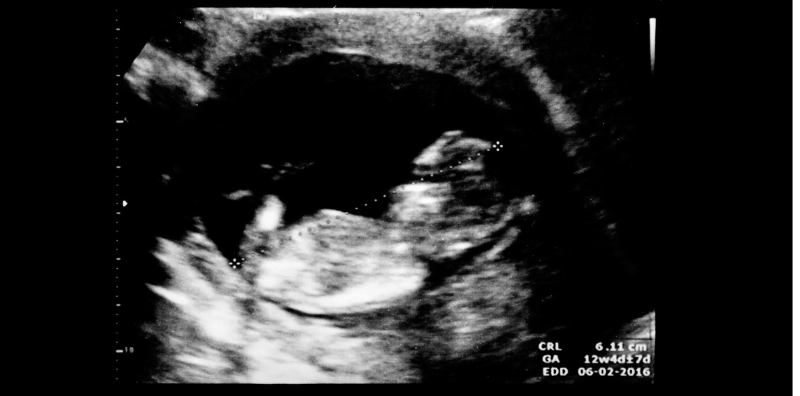

During pregnancy, one of the important signs of checking the health of the fetus is the movement or movement of the baby. The movement of the baby in the womb is something that the mother can observe. But sometimes, the change in movement can be a warning sign indicating a health problem of the baby or pregnancy that needs to be monitored. Today, let’s study together  about what kind of baby movement is dangerous.

When does a baby start moving in the womb?

Fetal movement is an important movement for monitoring the health and growth of the fetus. The baby will start to show movement periodically after the baby’s nervous system and muscles have developed and matured sufficiently. Generally, it starts to learn to move around in the fourth month of pregnancy. This movement is a signal that helps the mother to be aware of the growth and health of the baby more easily.